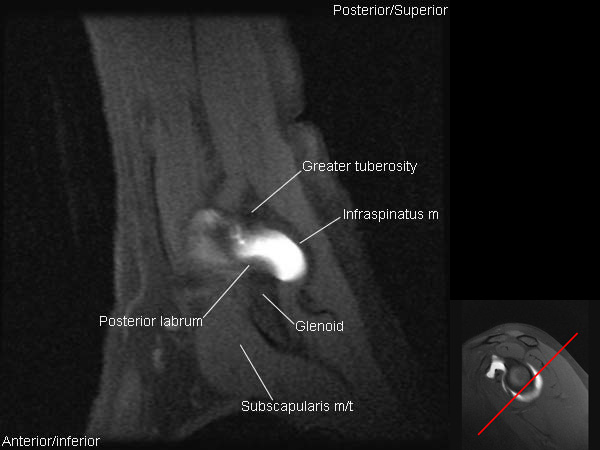

MRI Shoulder Arthrogram Anatomy

Arthrogram Anatomy